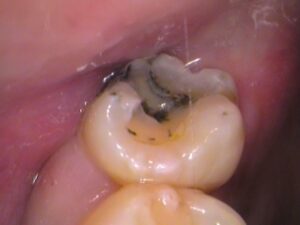

虫歯をすべて取り除き、歯の形を整えます。

虫歯は神経までは達していませんでした。良かったですね。

虫歯の深い箇所はレジンでコーティング保護してあります。

歯の中が綺麗になりましたね!

あとは歯型を取ってセラミックインレー(部分的な詰め物)を製作します。